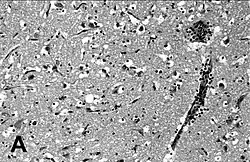

Encephalitis in the cerebral cortex of a harbor seal with PDV, stained with hematoxylin and eosin